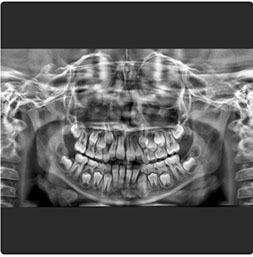

Radiografía Panorámica Digital

Radiografía Panorámica